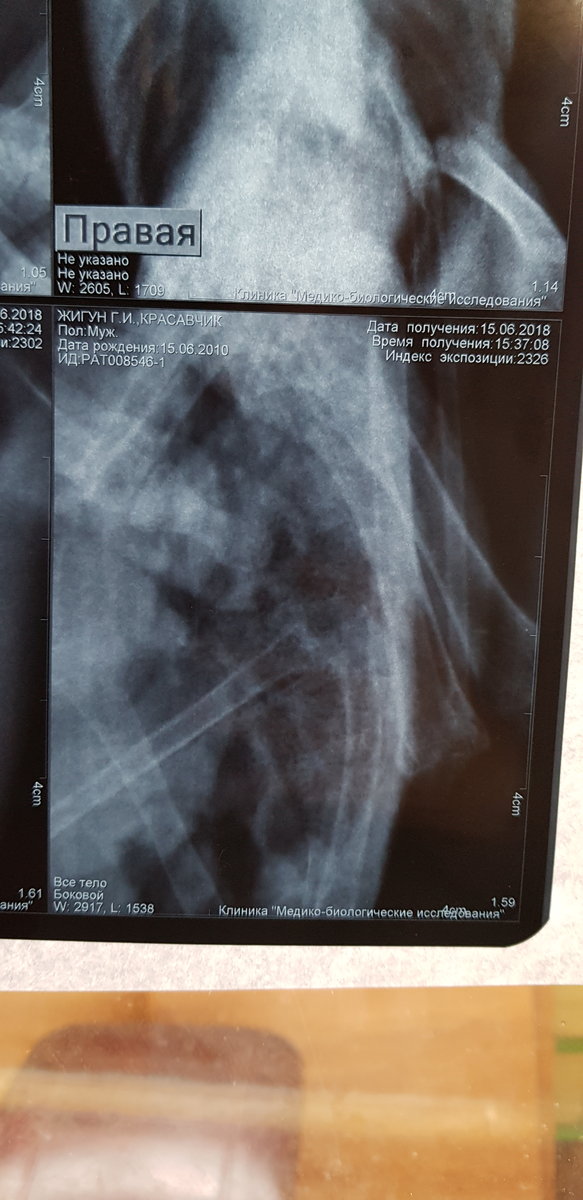

Сделала рентген. Но я в нем не разбираюсь.  Есть ли там грибы в легких. 3 дня по чуть-чуть совсем так чтобы выходило примерно 5 по на день орунгамин. И сейчас ему совсем плохо. Один глаз закрыт, помутнеет. Постоянно пытается отрыгнуть или делает такие движения. Совсем вялый. Фото прикреплю в сообщении ниже